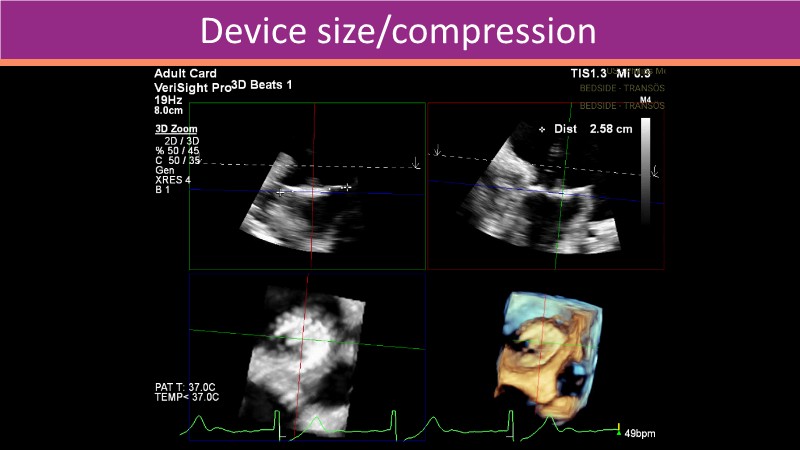

This PCR London Valves 2025 session explores how 3D TEE, 3D intracardiac echocardiography (ICE), and DeviceGuide technology sharpen procedural accuracy, strengthen operator confidence, and streamline decision-making in real time.

The session also includes detailed case analyses—such as Mitral TEER and LAA closure—and dual perspectives from both proceduralists and imagers.